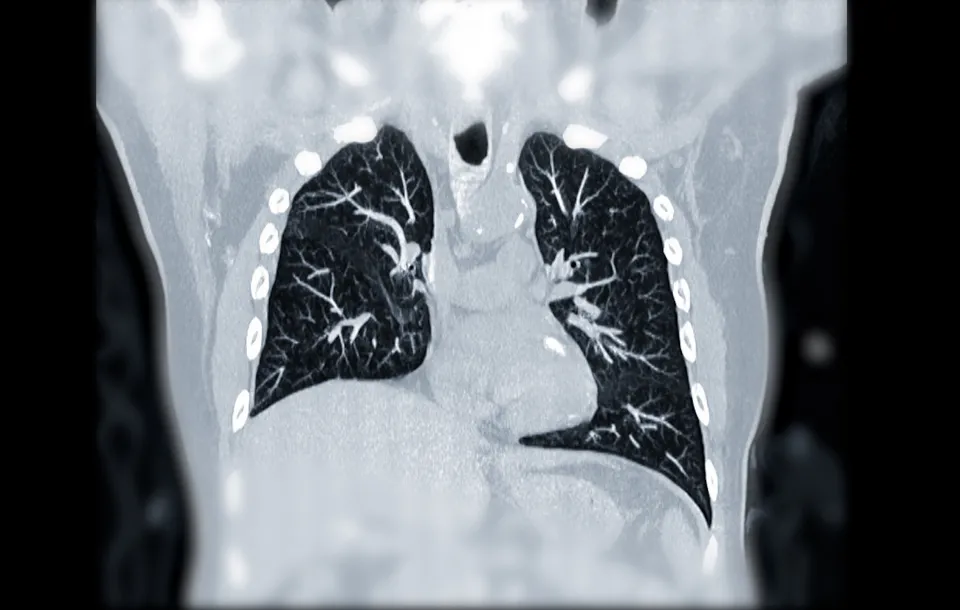

This webinar focuses on two critical pulmonary emergencies encountered in the emergency room: pneumothorax and pulmonary embolism (PE). Participants gain a deep understanding of the clinical presentation, risk factors, and complications associated with these conditions. The role of computed tomography (CT) imaging in diagnosing and evaluating pneumothorax and PE is emphasized, highlighting its advantages and limitations. Specific CT findings for pneumothorax and PE are discussed, enabling participants to accurately interpret and assess the severity of these conditions. The session concludes with a comprehensive overview of clinical management strategies for pneumothorax and PE.

ER pulmonary emergencies focus on the evaluation of PE and Pneumothorax with CT